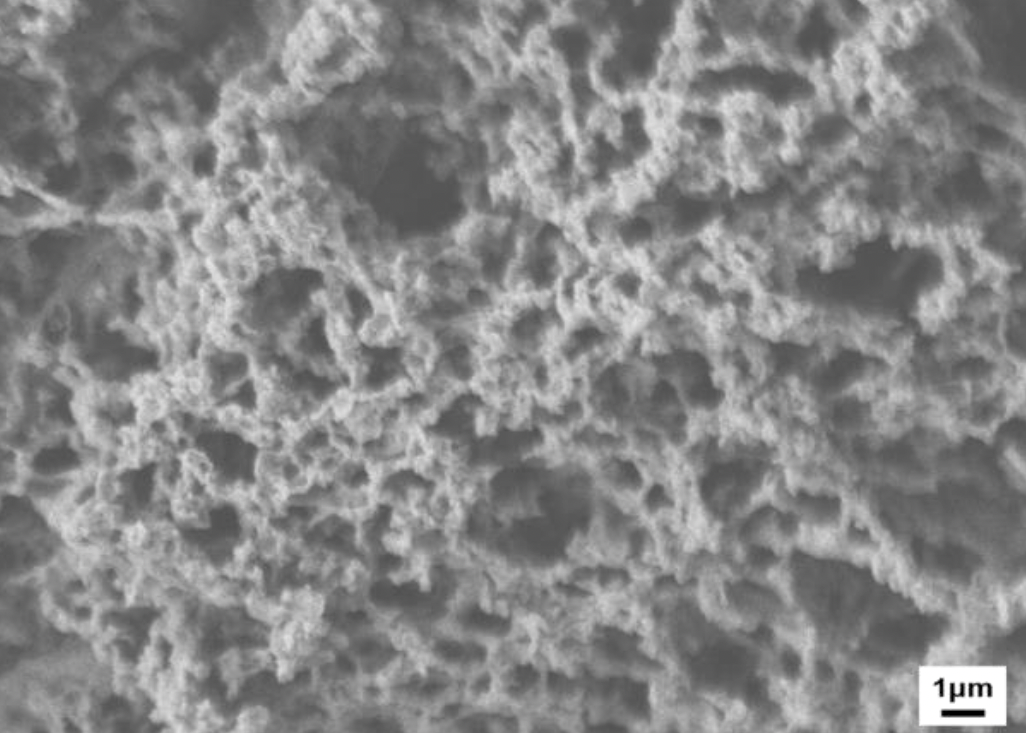

G4Derm Plus Mimics the Native ECM2,7

Native ECM

Scanning Electron Microscopy (SEM) magnification 5,000x and 270x, respectively.